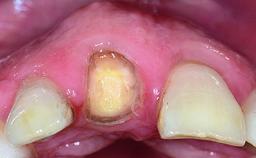

Replacement of a Failing Upper Left Central Incisor: Immediate Placement of an RC Bone Level Implant and Provisionalization

A healthy 23-year-old female patient was referred for a consultation on replacing tooth 21 with an implant-supported restoration. The patient had recently moved to the area and reported a history of endodontic and periodontal treatment for tooth 21. The tooth had been deemed non-restorable by her previous periodontist but since she was going to be moving, he recommended consulting to a dentist in her new city to continue her treatment. A review of her medical history yielded no significant findings and no known drug allergies. The analysis of her smile revealed a medium to high symmetrical smile line and a slightly discolored tooth 21.